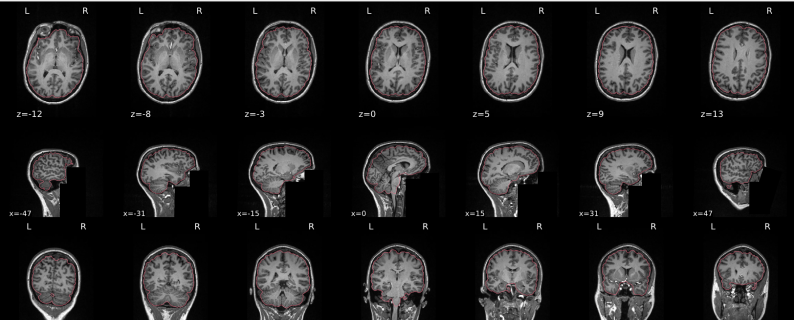

T1w skull stripping

Skull stripping is the process separating the brain (cortex and cerebellum) from the skull. The red line follows the outline of the brain and it separates it from the skull.

Example of a good subject

- There are no skull stripping errors, such as portions of the brain missing, or too much of the skull retained

- The red line follows the outline of the brain

Example of a bad subject

- There are skull stripping errors, such as portions of the brain missing, or too much of the skull retained

- NOTE: check all the images (slices) in the report. If only one image (slice) looks problematic, it is possible that the subject is okay and it is just a visual issue in that particular screenshot

Summary

| Good | Bad |

|---|---|

| The brain is fully inside the red line | Structures like the cranium or the eyes are inside the red line |

| No important brain structures are outside of the red line red line follows the natural outline of the brain | Important brain structures are missing inside of the red line |

-> if only one slice is problematic, it could be an issue related to the visual depiction of the data instead of an issue related to the test subject